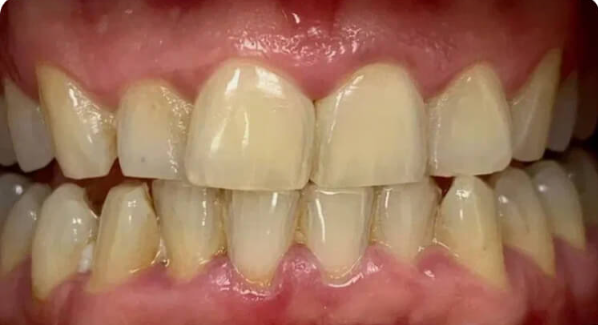

На странице представлено портфолио стоматологий Санкт-Петербурга с работами до и после профессиональной чистки зубов. В нашем портфолио собраны разные клинические случаи: от удаления незначительного налета до снятия массивного поддесневого камня. Здесь вы можете увидеть, как возвращается естественный цвет и внешний вид зубов после процедуры. Изучите результаты до и после чистки зубов, чтобы увидеть реальный эффект и выбрать клинику в Санкт-Петербурге, где профессиональная гигиена поможет вернуть зубам здоровый вид.